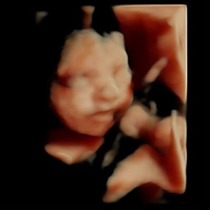

Went for a 4d scan today and got some fantastic piccies of my baby girl .... Heres sone for those not on fb.

June 2015 - bumps ahoy!

Ahh jazzy they are lovely...... Grin

Thanks chook, we were amazed at the images we got, never had 1 before and would totally recommend it.

She did lots of baby checks aswell and gave us a weight and length estimate.